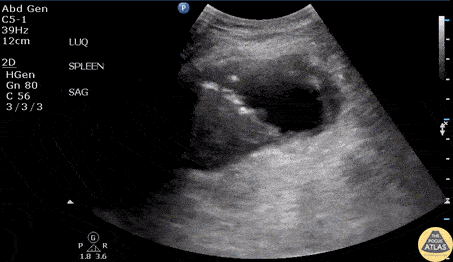

Bowel-GI - Splenic Abscess

An elderly male with a history of IVDU presented to the ED with fever and abdominal pain. Vital signs reveal hypotension. RUSH examination revealed a splenic abscess viewed in the perisplenic window. Image courtesy of Robert Jones DO, FACEP @RJonesSonoEM Director, Emergency Ultrasound; MetroHealth Medical Center; Professor, Case Western Reserve Medical School, Cleveland, OH View his original post here